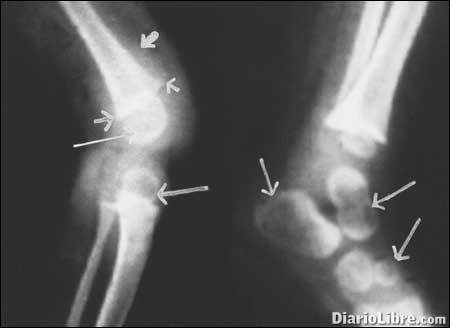

Entre los síntomas menciona, el dolor o sensibilidad en los huesos, las deformidades esqueléticas, piernas arqueadas, proyección del esternón hacia adelante (pecho de paloma), protuberancias en la caja torácica (rosario raquítico), cráneo asimétrico o de forma extraña, deformidades de la columna (curvas de la columna anormales, incluyendo escoliosis o cifosis), deformidades pélvicas, aumento de la tendencia a las fracturas óseas, deformidades dentales, retraso en la formación de los dientes, defectos en la estructura de los dientes, perforaciones en el esmalte, aumento en la incidencia de caries en los dientes (caries dentales), debilidad progresiva, disminución del tono muscular (pérdida de la fuerza muscular), calambres musculares, crecimiento deficiente, baja estatura: adultos menos de 1,52 m (5 pies) de alto